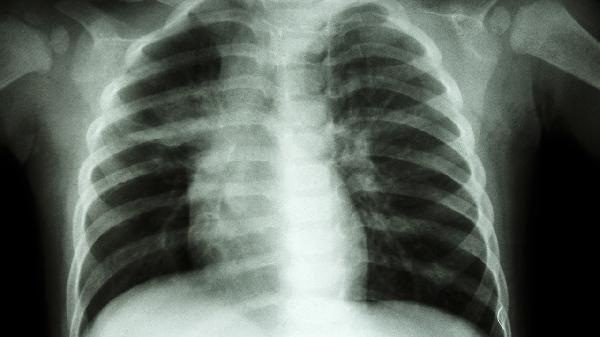

Adson试验阳性表现为桡动脉搏动消失,Wright试验在过度外展上肢时诱发症状,Roos测试通过持续抬臂动作可复制疼痛。这些体格检查有助于临床诊断,但需结合影像学检查排除颈椎病等疾病。